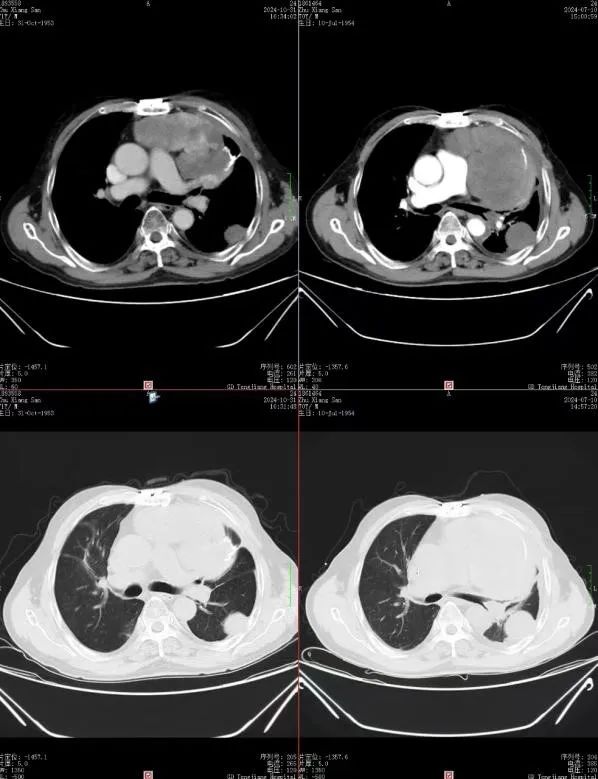

01 朱先生是一位与肺恶性肿瘤抗争多年的勇士。自确诊以来,他经历了多次复发和反复手术。2021年3月,胸部CT揭示了左下胸腔的占位性病变,随后的肺肿物切除术和化疗未能阻止病情的进展。2023年,局部复发再次降临,尽管再次手术和化疗,顽固的低血糖和双下肢浮肿等问题仍旧困扰着他。2024年6月,胸部CT显示肿瘤进展,胸膜心包膜受累,7月症状加重,他带着朋友的推荐来到我院寻求帮助。 AUTUMN 在朱先生的治疗旅程中,我们深刻理解他的痛苦与焦虑,并承担起责任。我们的专家团队为他量身定制了治疗方案:首先采用LATTICE技术精确打击肿瘤,结合替莫唑胺化疗、培唑帕尼抗血管治疗及激素压制的综合治疗方案。经过6次LATTICE治疗后,朱先生的病情得到了显著改善——肿瘤缩小,血糖稳定在正常水平,生活质量大幅提升。如今他已出院两月有余,享受着与家人共度的美好时光。这一成功案例是ky多学科会诊模式下,精准放疗中心和肿瘤科技术团队紧密合作的结果 探索革命性的LATTICE技术 LATTICE技术,即空间分割放射治疗技术,以其在肿瘤内部创造不均等剂量分布的原理,为肿瘤治疗领域带来新突破。这种先进的放射疗法特别适用于大肿块(任何尺寸≥5 cm)和放射抗性肿瘤,展现出其独特的优势:高剂量区精准定位于肿瘤内部,同时最大程度保护正常组织;显著改善症状;确切的肿瘤消退效果;以及卓越的局部控制率。